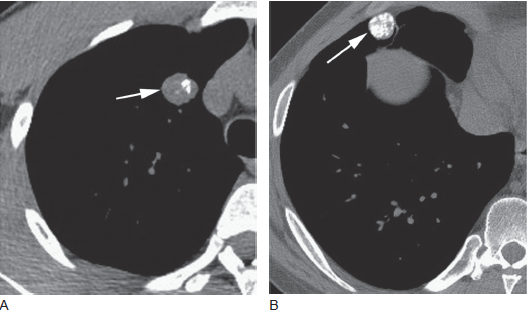

图3 在三个病例中,错构瘤都含有脂肪

在结节中( 箭头),可见局灶性的低衰减的含脂肪区域,这些结节是圆形的,而且边界清楚